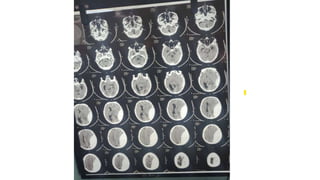

Volume calculation

• For the bedside ,as suggested by kothari : ABC/2

• A: the largest area of hemorrhage on the slice

• B : the largest diameter 90 degree to A om same slice

• C : Approximate number of CT slices with hemorrhage multiplied by slice

thickness

• The ABCs of measuring intracerebral hemorrhage volumes R U kothari et al.1996 Aug

• C is calculated by a comparison of each CT slice with hemorrhage to the CT slice

with largest hemorrhage on that scan

• If the hemorrhage area > 75 %,slice is considered 1 hemorrhage slice

• If the hemorrhage area is approximately 25% to 75 % ,1/2 hemorrhage slice

• If the hemorrhage area < 25 % of the largest hemorrhage ,the slice is not

considered as hemorrhage slice